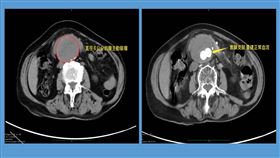

胃癌圍手術期免疫治療7旬婦恢復進食能力

「心臟掉到肚子!」阿嬤經檢查發現…

「醫師,怎麼辦 ? 我的心臟掉到肚子!」83歲的阿嬤...